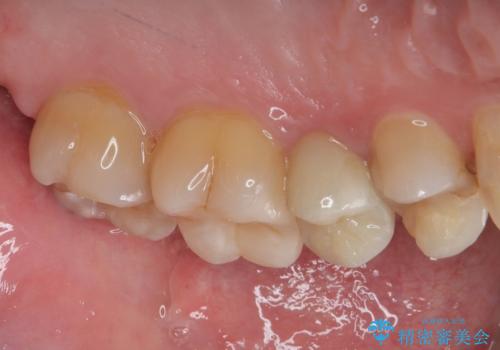

歯と歯茎の間に圧排糸と言われる糸を入れてシリコーン印象材にて精密な型どりをしました。

セラミックインレーの装着時には、唾液の侵入を防ぐために、ラバーダム防湿を行いました